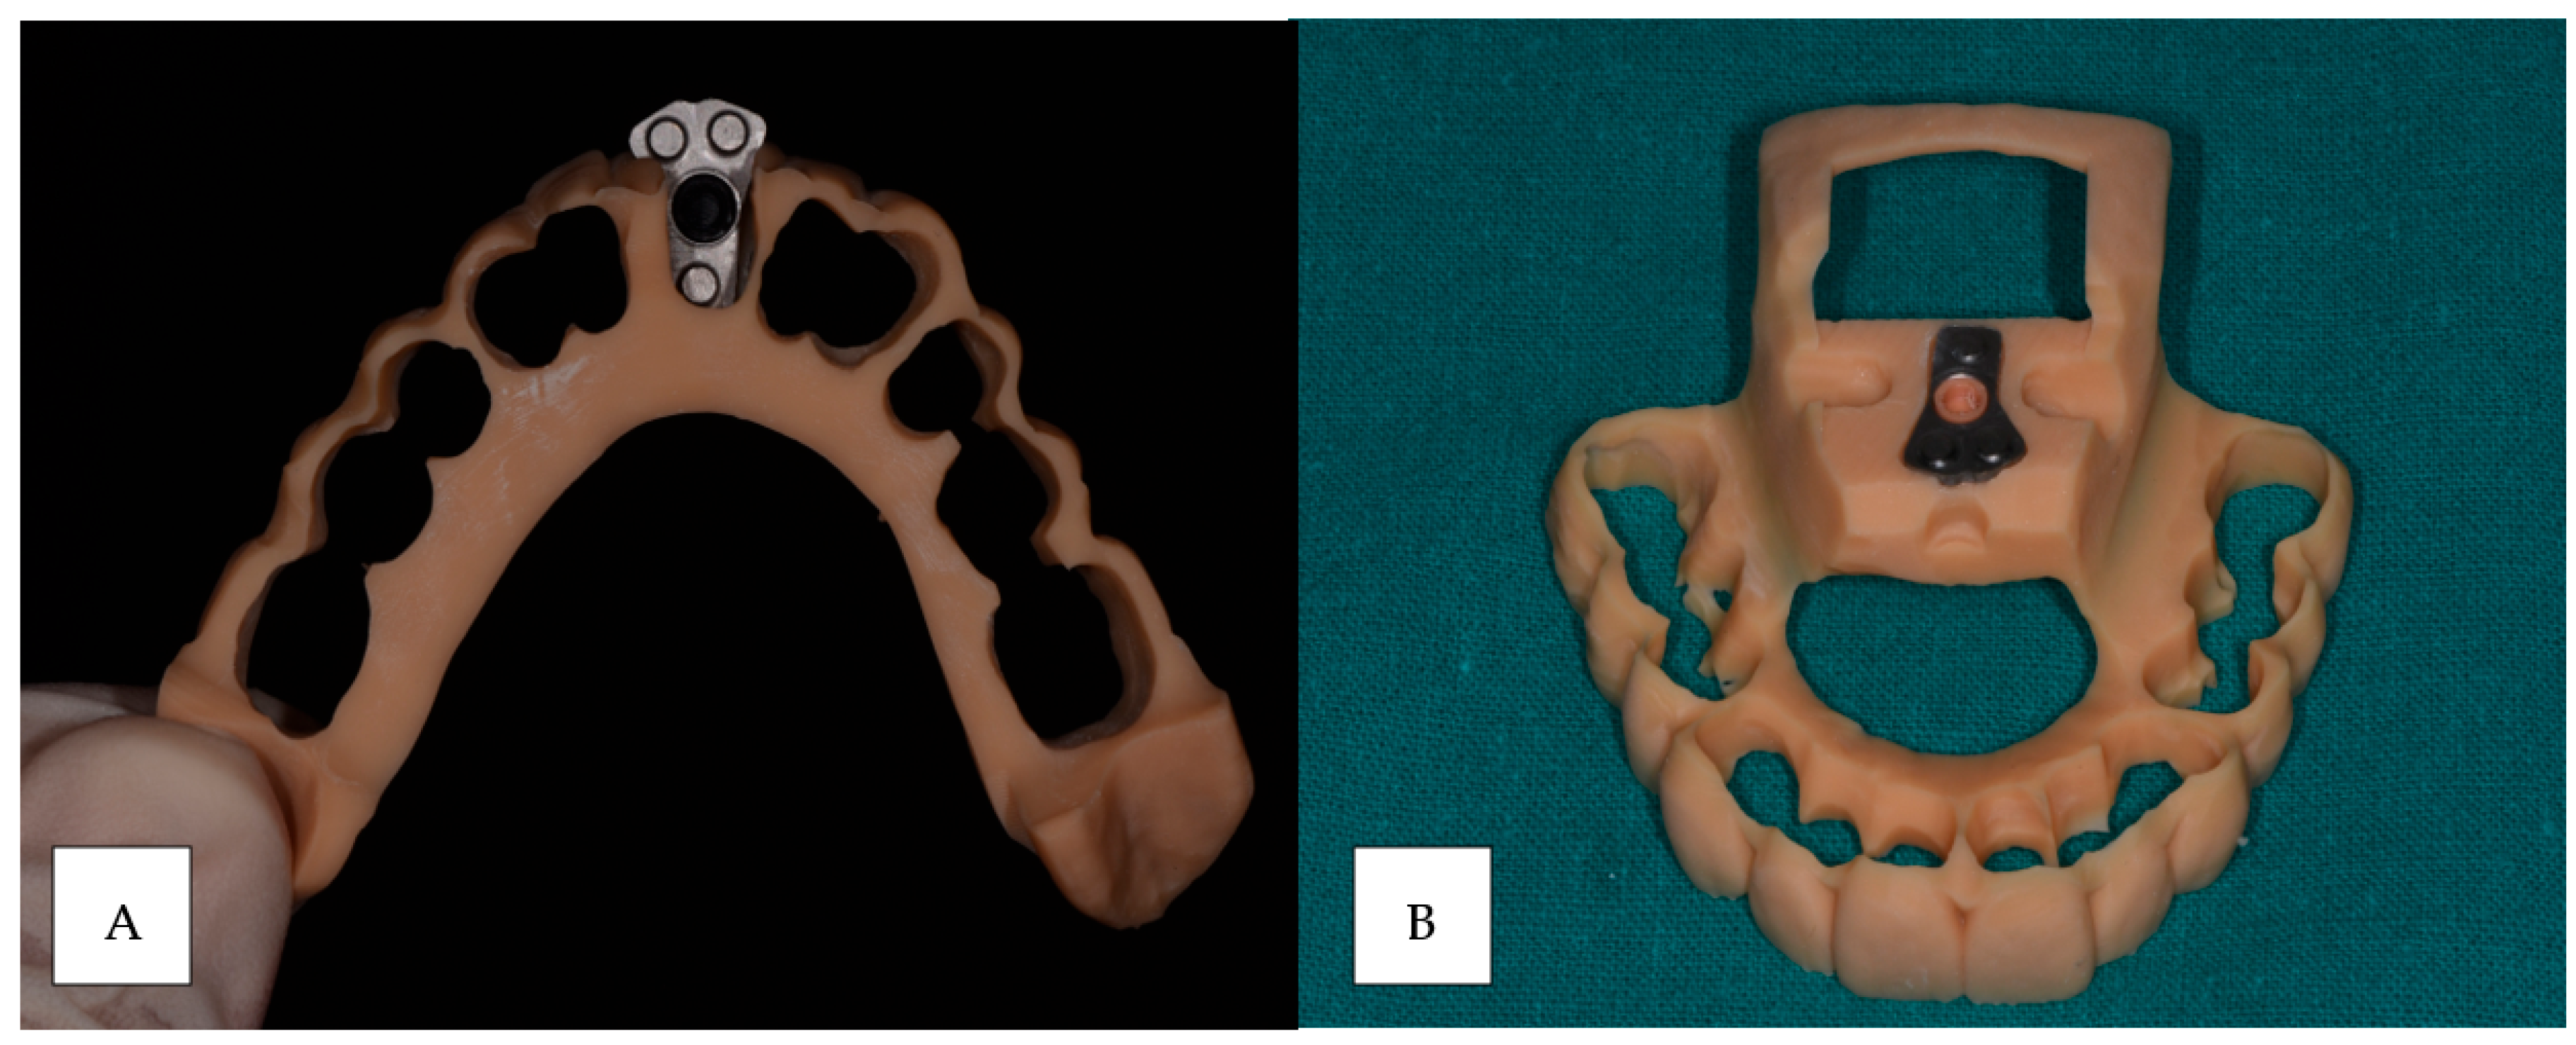

2.2. Impression Reference Technique Device